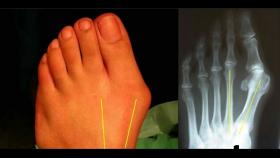

骑行课堂 | 出现这种症状立马治疗 否则只有定制锁鞋一条路

大多数中国人的脚型较宽,因此部分品牌有针对亚洲市场推出宽版锁鞋,即使常规尺码较宽的Bont锁鞋也不例外。但实际上有非常大一部分人群的宽脚是由于疾病而导致的,严重者甚至连宽版锁鞋都穿不上,只剩下定制锁鞋一条路。如果你也患上了这样的症状,赶紧治疗!